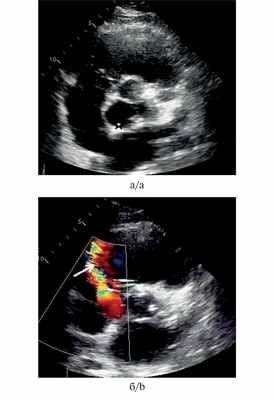

Рис. 2. Трансторакальная эхокардиография у пациента И. (короткая ось на уровне корня аорты).

а — аневризма некоронарного синуса Вальсальвы (показана звездочкой); б — дефект стенки аневризмы со сбросом крови в правое предсердие (показан стрелкой).